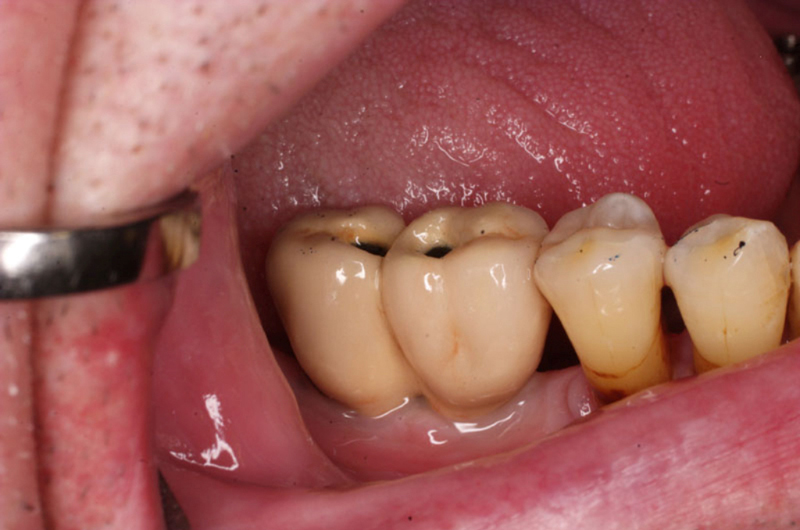

V případě chybění většího počtu zubů v postranních úsecích čelistí je možné ošetření pomocí implantátů, které nahradí ošetření pomocí snímacích náhrad kotvených na zbývajících zubech nebo patře.

Podmínkou je opět dostatečné množství kosti.

Protetické řešení může být pomocí můstku, který je kotvený na implantátech nebo pomocí jednotlivých korunek na implantátech.

V zásadě je možné do těchto můstků zařadit i přirozené zuby, zejména pokud je potřeba tyto zuby ošetřit proteticky

- korunkami. Korunky nebo můstky mohou být na implantáty nacementovány nebo přišroubovány.

Zdravé zuby zůstanou zachovány a přitom náhrady jsou pevné, jako na vlastních zubech